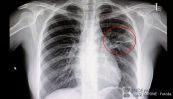

Viêm phổi do sặc xăng dầu tuy là bệnh hiếm gặp - chủ yếu xảy ra với những người thợ lái máy công trình do không tuân thủ an toàn lao động đã dùng miệng hút xăng, dầu bị sặc, nhưng lại gây hậu quả tổn thương phổi nặng nề. Cùng eLip tìm hiểu ngay bài viết dưới đây để hiểu rõ hơn nhé!